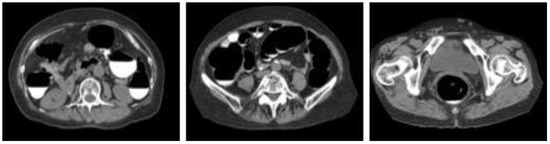

3.1. Cleansing Images Generated Using CycleGAN